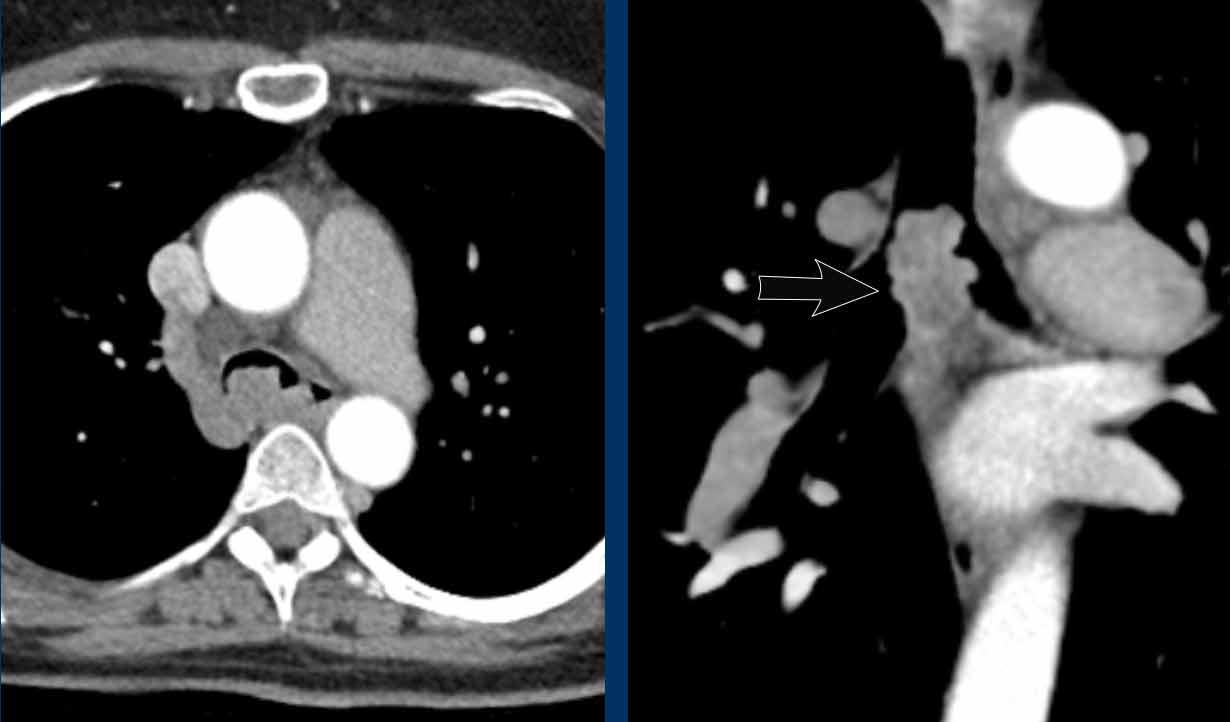

Cung động mạch chủ đôi

Bệnh nhân này có cung động mạch chủ đôi gây chèn ép khí quản.